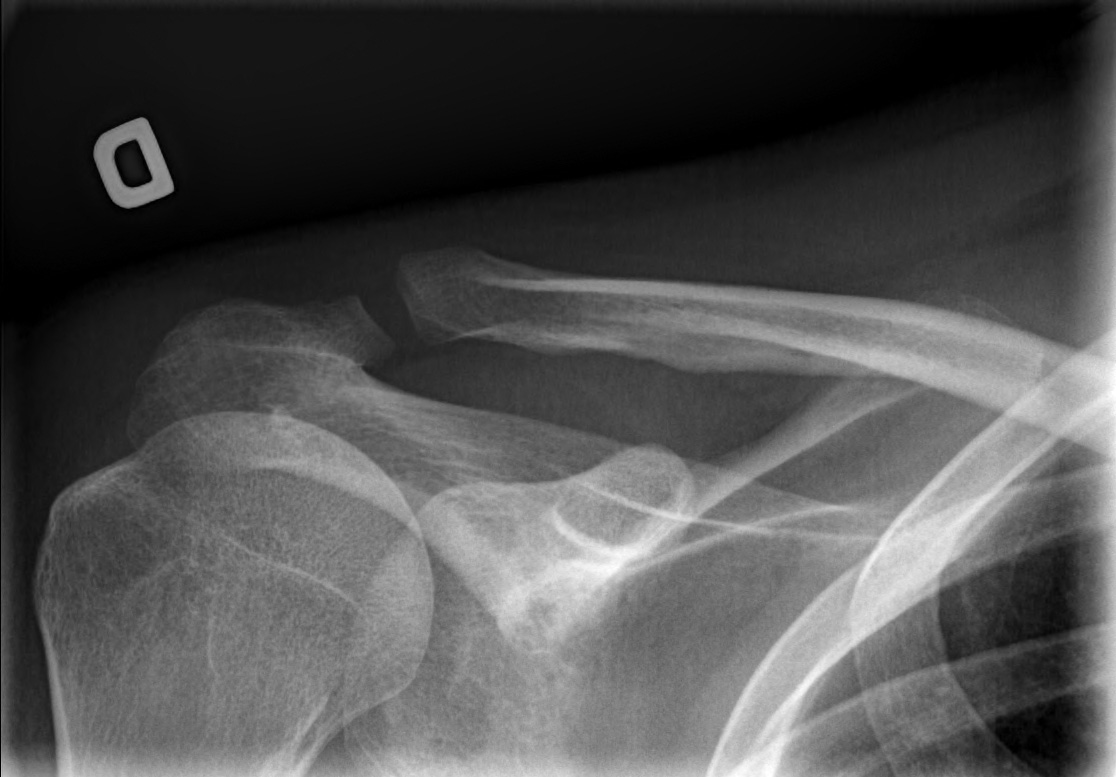

27-year-old male:

Left shoulder pain following a direct fall on the shoulder.

Acromioclavicular luxation

Bone misalignment

The left clavicule is displaced superiorly with increased acromioclavicular and coracoclavicular distance relative to the right side.

Displacement measurement

Superior displacement of the left clavicle with a coracoclavicular distance of 32 mm compared to 13 mm on the right side (146% displacement). This is thus a grade 5 acromioclavicular joint dislocation.